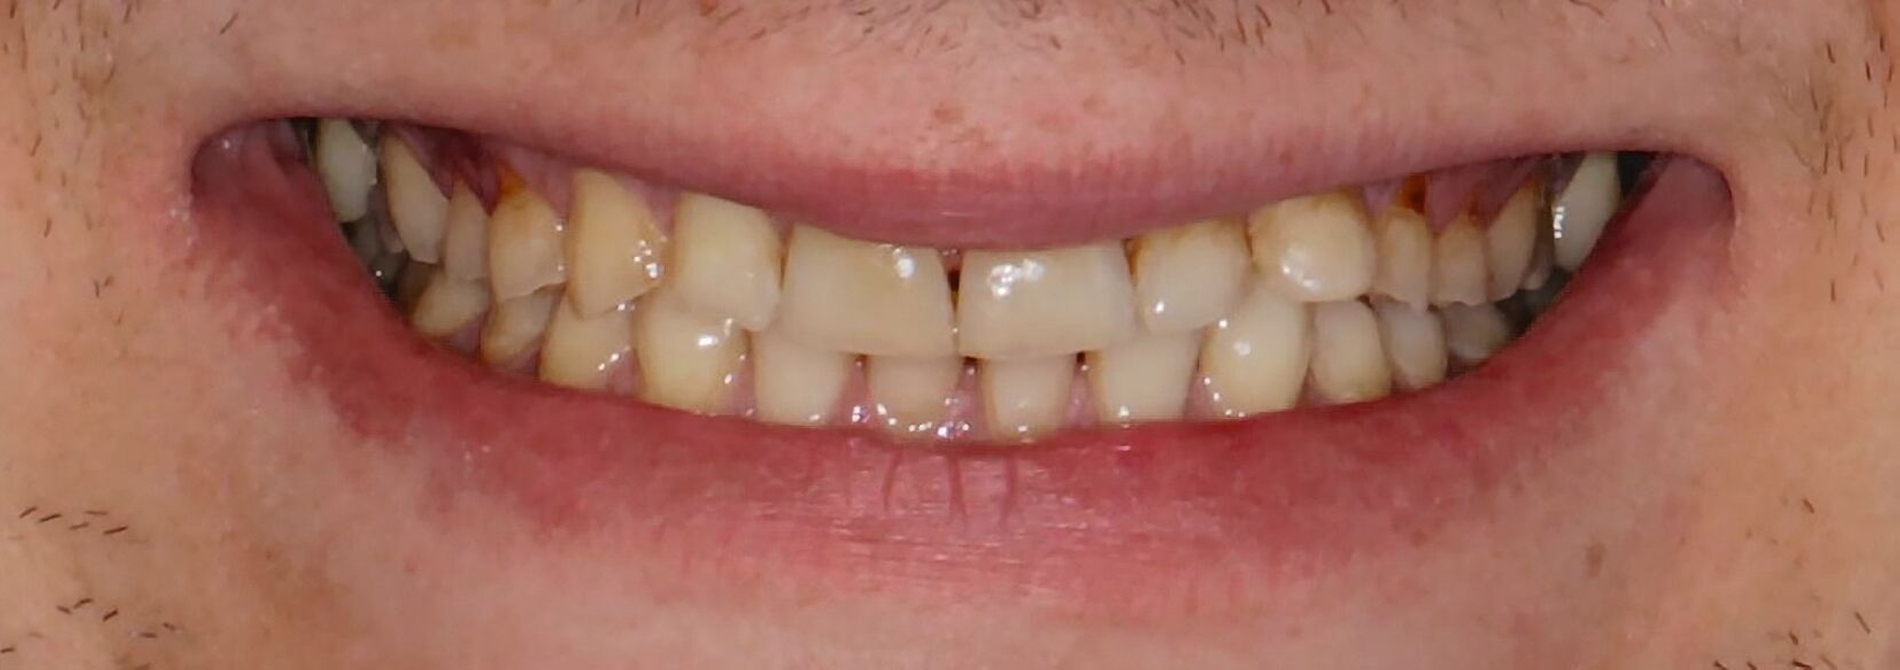

Ein Profi-Fußballspieler stellte sich in der Praxis zur sportzahnmedizinischen Überprüfung vor. Er klagte über Schmerzen an der linken Patellasehne. Sowohl in Ruhe als auch während Belastung beim Training oder im Spiel hatte der Sportler Probleme und immer wiederkehrende Schmerzen.

Allgemeinanamnestisch bestanden bei dem Athleten keine Auffälligkeiten. Es gab in der Vergangenheit keine kieferorthopädische Behandlungen und bis auf kleinere, konservierende Versorgungen auch keine invasiven Zahnbehandlungen. Die Auswertung des ausgefüllten DGSZM-Befundbogens ergab Auffälligkeiten in den Bereichen CMD-Kurzbefund und den sportspezifischen Fragestellungen (Patellasehne).

Bei der visuellen Kontrolle der Okklusion mithilfe von Okklusionspapier (40 mm) und Shimstockfolie (8 mm) konnte am Abhang des distobukkalen Höckers des Zahns 37 ein dynamischer Vorkontakt während der Laterotrusionsbewegung festgestellt werden. Im Stehen war die Kopfrotation nach links im Vergleich zu rechts eingeschränkt und es war eine leicht hochgezogene linke Schulter zu erkennen.

Weiterhin konnte bei geschlossener Zahnreihe in maximaler Interkuspidation eine leichte Mittellinienverschiebung der Unterkiefer- zur Oberkiefermitte von etwa 1,5 mm festgestellt werden. Schon bei leichter Mundöffnung glichen sich die jeweiligen Mitten an – ein weiterer Hinweis auf ein Okklusionshindernis.

Die Palpation der Kaumuskulatur zeigte einen asymmetrischen Muskeltonus der Mm. Masseteres, wobei der rechte M. Masseter einen deutlich stärkeren Muskeltonus aufwies als der linke. Auch die Palpation der Mm. Pterygoidei war beidseits positiv.